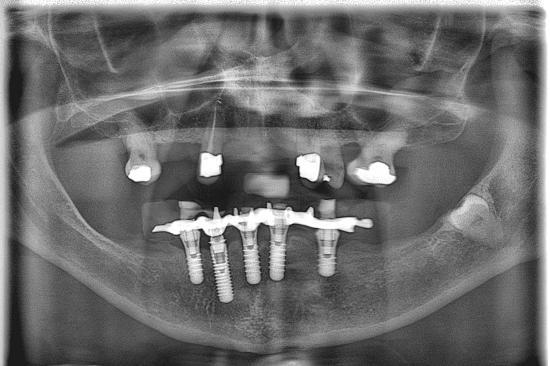

When we jump forward to where we are now, 12 years later, so much has changed with how we provide our implant dentistry.

Dare I say it, this is the sum of the aggregation over the years of all of our marginal gains.

Here is a more recent case…

Not only have we honed our techniques and are using the better, modern equipment available to us, but our systems and processes allow us to work smarter, not harder.

In turn, this leaves us time to focus on working on the next one per cent improvement.